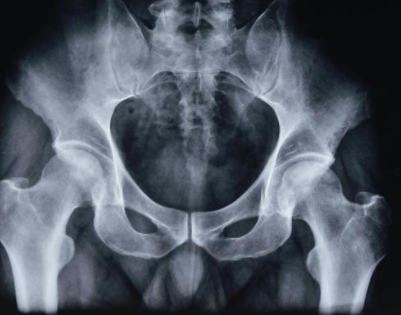

河南治疗股骨头坏死医院讲解早期股骨头坏死的临床表

河南治疗股骨头坏死医院介绍到通常在早期出现股骨头坏死时我们都有疼痛的症状,疼痛往往是…[详情]